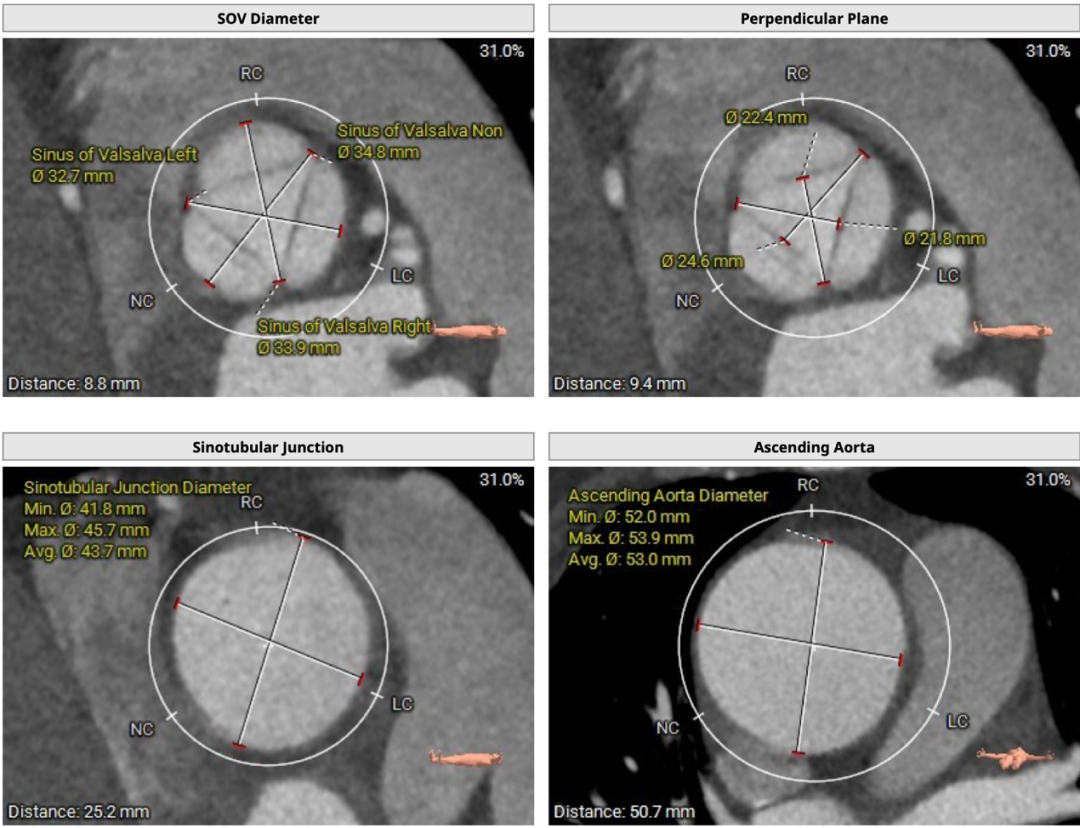

CT分析

患者主动脉瓣三叶式,瓣叶基本等大,瓣叶不厚,瓣叶未见明显钙化。主动脉瓣环周长折算直径约24.6mm:

左侧冠脉开口高度低,LCA 9.8mm,左冠瓣瓣叶长度约12.8mm;右侧冠脉开口高度可,RCA 14.3mm:

术中建议造影角度RAO 7°,CAU 14°(其它参考角度如下图):

升主动脉瘤样扩张,最大径53.9mm,窦管交界增宽:

主动脉弓、降主动脉及双侧髂总动脉见多发钙化;胸主动脉迂曲;心室角度57°: